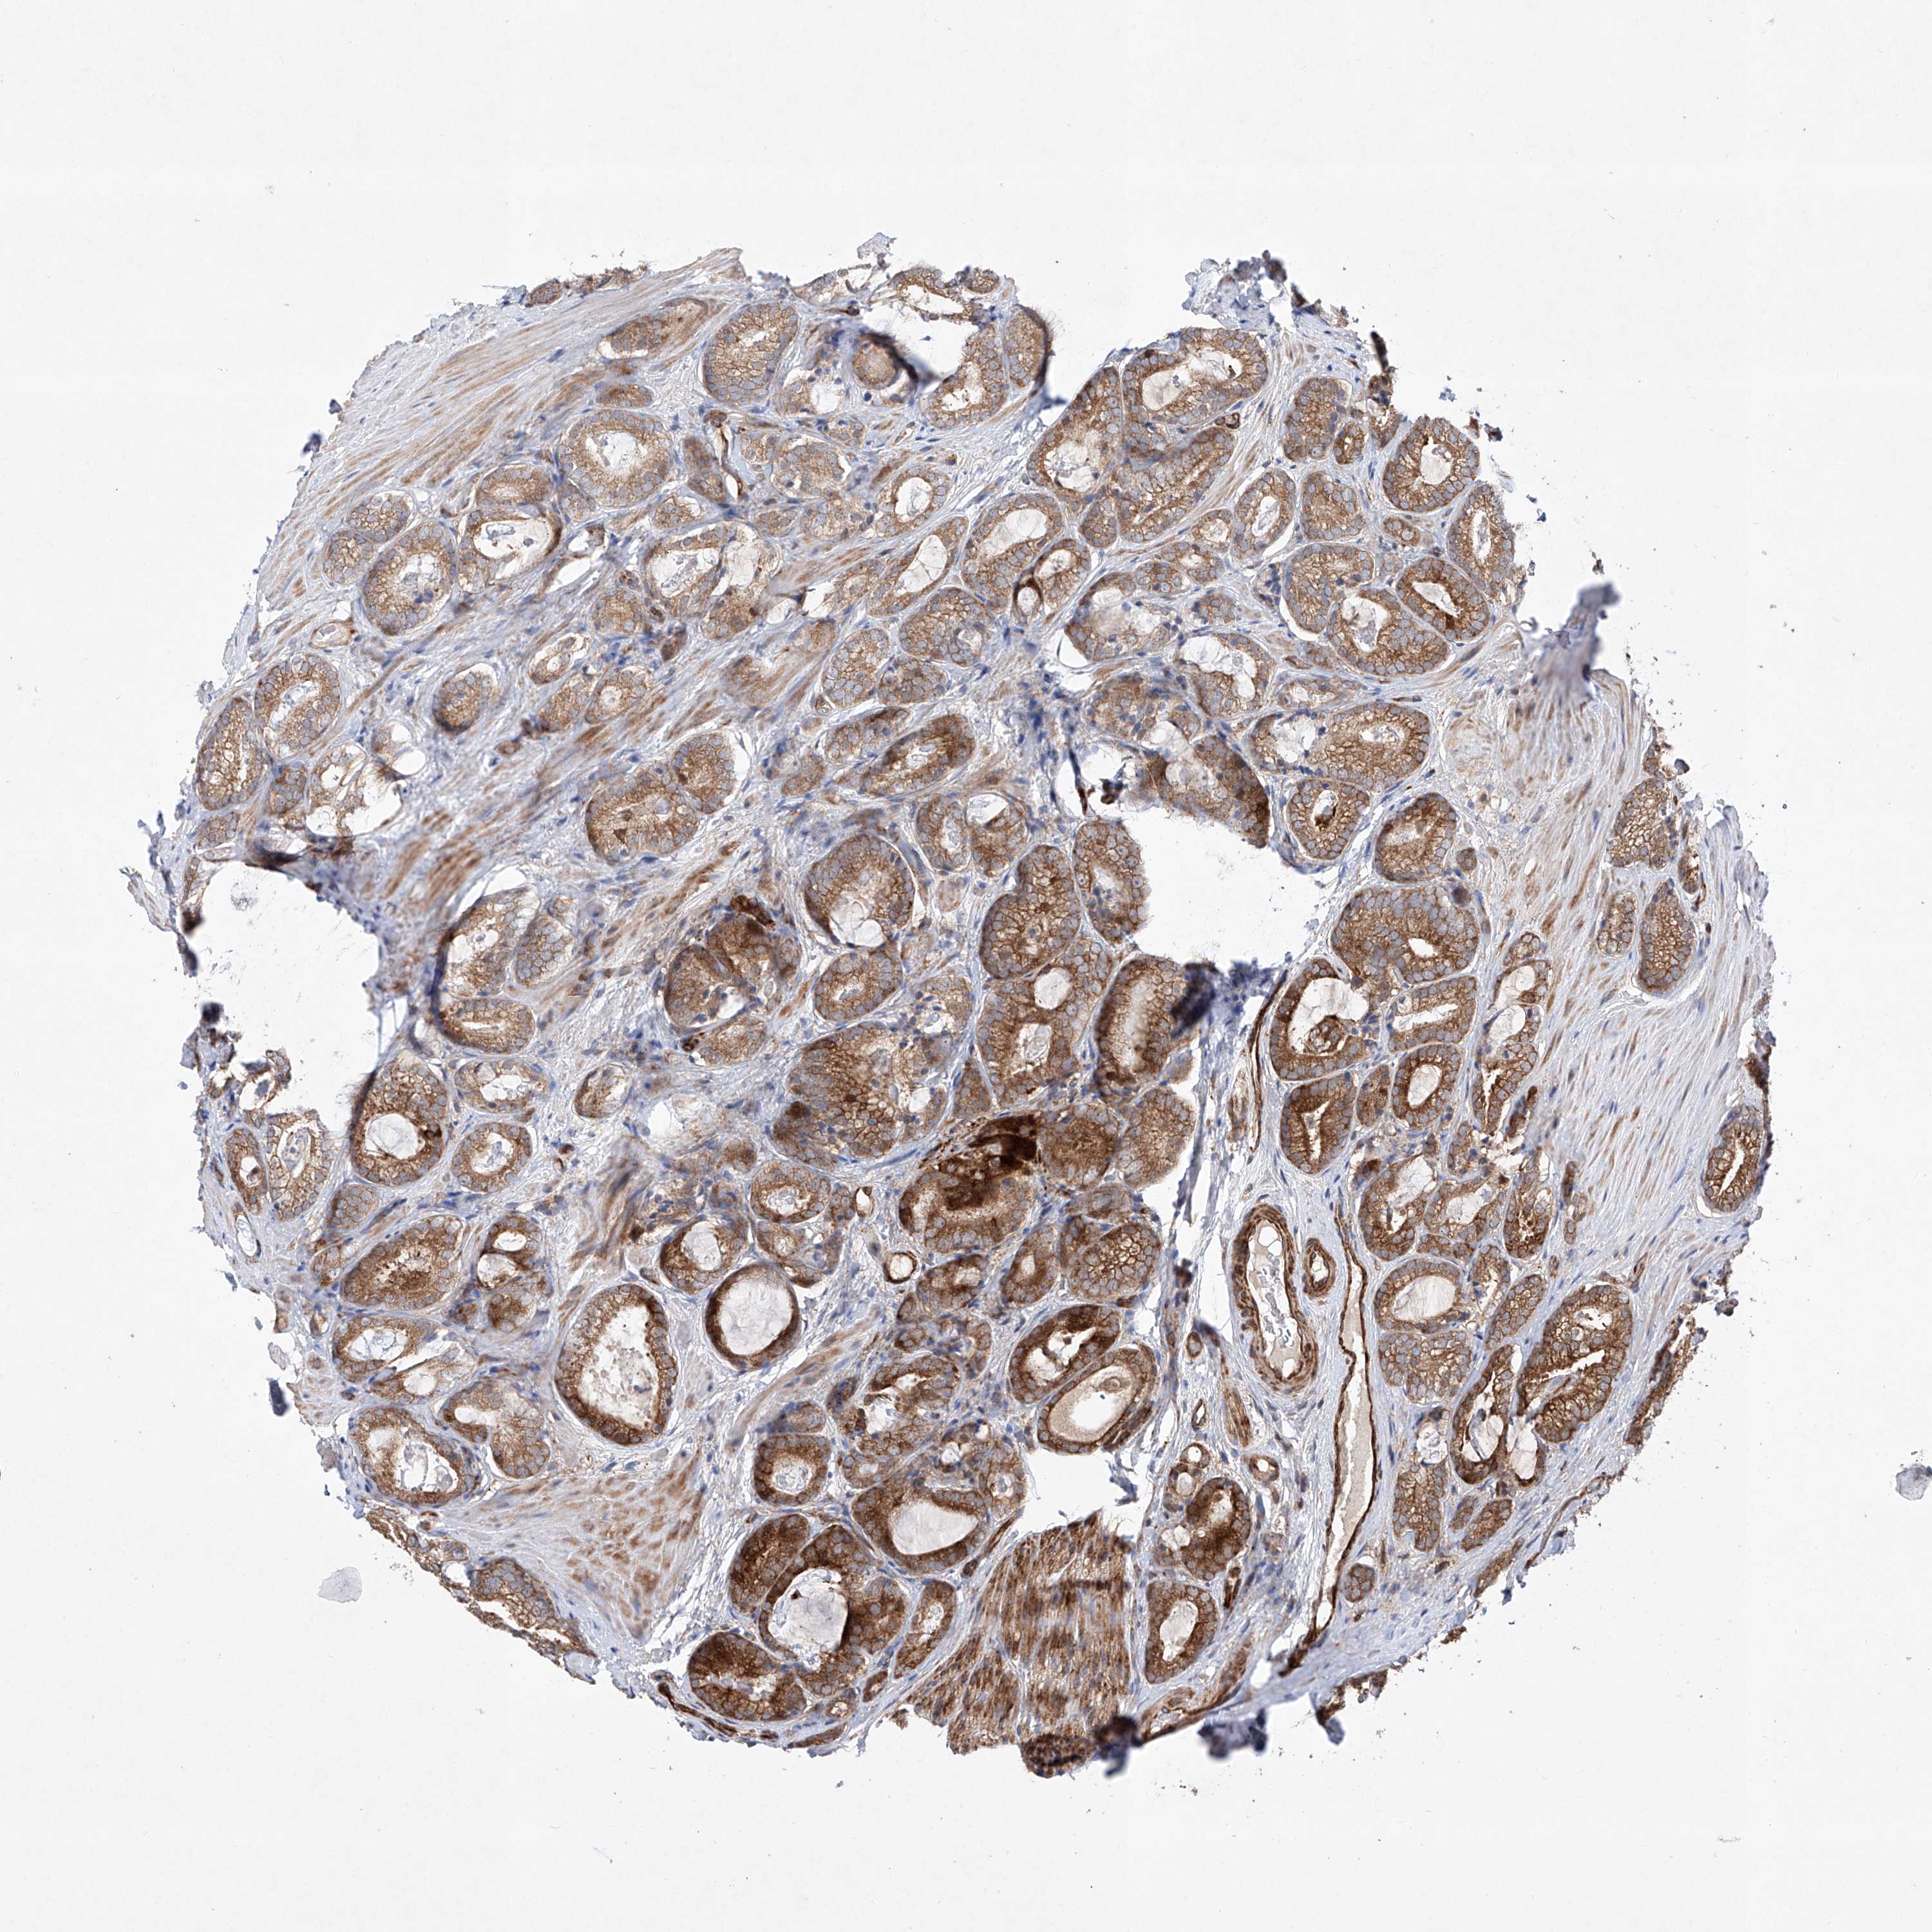

PROSTATE CANCER - Protein expressioni

A mouse-over function shows sample information and annotation data. Click on an image to view it in a full screen mode. Samples can be filtered based on level of antibody staining by selecting one or several of the following categories: high, medium, low and not detected. The assay and annotation is described here.

Antibody stainingi

Antibody staining in the annotated cell types in the current human tissue is reported as not detected, low, medium, or high, based on conventional immunohistochemistry profiling in selected tissues. This score is based on the combination of the staining intensity and fraction of stained cells.

Each image is clickable and will lead to virtual microscopy that enables deeper exploration of all samples and also displays staining intensity scores, fraction scores and subcellular localization as well as patient and tissue information for each sample.

Antibody HPA031408

Staining

High

Medium

Low

Not detected

Intensity

Strong

Moderate

Weak

Negative

Quantity

>75%

75%-25%

<25%

None

Location

Nuclear

Cytoplasmic/membranous

Cytoplasmic/membranous,nuclear

Adenocarcinoma, High grade

Adenocarcinoma, Low grade